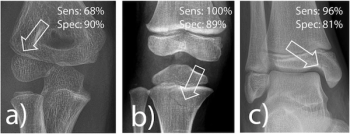

Artificial intelligence (AI) software demonstrated a 92 percent sensitivity for detecting fractures in a study involving over 1,600 X-rays from a tertiary pediatric emergency department.